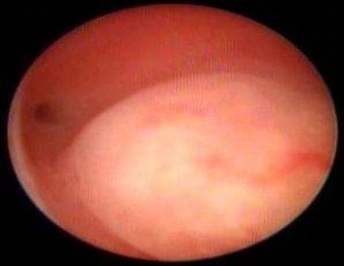

Hysteroscopy showing Nomal Uterine Cavity.

Three-Dimensional Ultrasonography (3D USG) in comparison to hysteroscopy is less invasive, cheaper, easily accepted by most patients and does not require much training. In most cases an endometrial polyp can be differentiated from the submucous fibroid based on the imaging characteristics. The polyps are typically round in shape, smooth in outline, and are generally echogenic, compared to the endometrium or are isoechoic to it. The underlying endometrial-myometrial interface is preserved (Figure 5). Moreover the presence of a vascular pedicle has a positive predictive value of up to 81.3%. Fibroids are more inhomogeneous, hypoechoic, and there is a loss of endometrial-myometrial interface. The percentage of the intra cavitary portions of the submucous fibroids i.e., grade of submucous myoma can be assessed on 3D USG by the degree of distortion caused by it (Picture 6).

Our study demonstrated that 3D TVS had high specificity, but its sensitivity was limited, especially for detecting endometrial polyp. A significant percentage of patients had evidence of uterine cavity pathology. As such, hysteroscopy remains the preferred procedure for accurate detection and diagnosis of uterine cavity lesion.

Hysteroscopy is an accurate and less invasive method for the evaluation of uterine cavity and allows direct visualization of the endometrium, revealing the nature, location, shape, size and vascular pattern of any uterine cavity abnormalities. Complications [11] such as vasovagal reaction, Uterine perforation, Cervical laceration, Haemorrhage, are rare with hyseroscopy. The patient may experience anxiety, discomfort, and mild lower abdominal cramps during hysterscope insertion. However, the symptoms subside soon after the end of the procedure. The procedure is usually tolerated well.